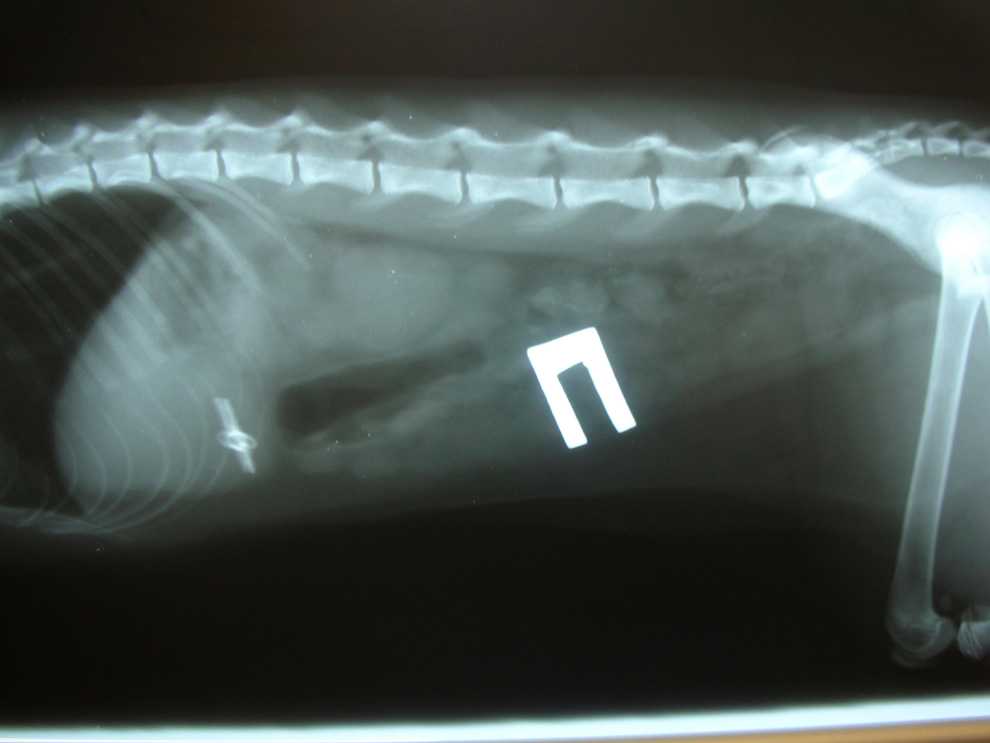

Если собака проглотила инородное тело прям при присутствии владельца, и он видел, какого рода предмет был проглочен, врач направляет пациента на прохождение ряда необходимых исследований. Опровергнуть или подтвердить точный диагноз позволяют инструментальные и лабораторные исследования. Проводиться следующий ряд мероприятий:

Рентгенографическое исследование. Позволяет выявить металлические изделия и предметы из резины

Даже без обнаружения инородного тела в кишечнике, специалист отмечает изменение анатомического положения внутренних органов, появляющееся при попадании посторонних предметов в организм животного.

Контрастная рентгенография. Исследование с применением специфического контрастного вещества. Позволяет визуализировать процесс продвижения инородного тела по пищеварительному тракту.

При отсутствии положительных результатов от вышеперечисленных методик, проводят эндоскопию. При помощи специального инструмента врач может визуализировать состояние поврежденных стенок желудка и кишечника, а также с высокой точностью определить место расположения проглоченного предмета – иглы, нити, целлофанового пакета.

- Рентгенография поможет выявить наличие металлических, резиновых предметов, камней. На рентгене также видна деформация и другие изменения в органах пищеварительного тракта, характерные для присутствия инородного тела.

- Чтобы точно определить место предмета и проследить его продвижение по пищеварительному тракту, делается рентген с контрастным веществом. Чаще используется барий.